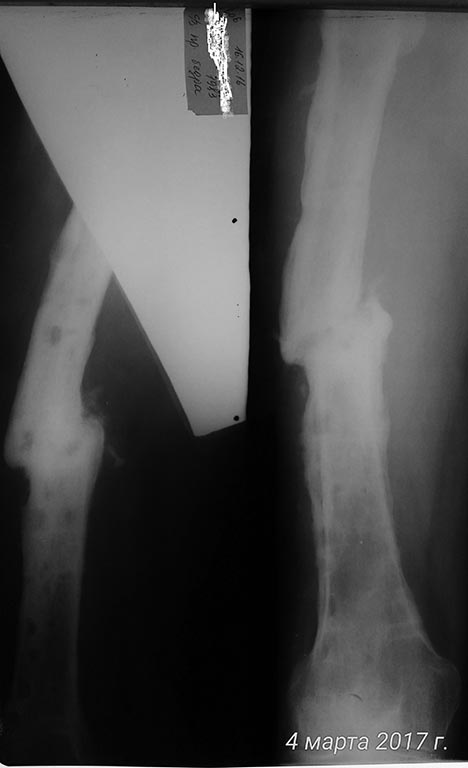

Локально при поступлении: по латеральной пов-ти ср/3 правого бедра п/о

рубцы, 2 свища с гнойно-геморрагическим отделяемым, дно - бедренная

кость. На рентгенограмме: перелом не сросся. Выполнена фистулография.